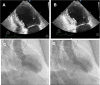

Echocardiogram pattern in a patient with TCM demonstrating apical ballooning and diffuse hypokinesis with sparing of the basal myocardial segments. Left ventricle in (a) end-diastole and (b) end-systole is shown; Left Ventriculogram pattern in TCM shown in (c) end-diastole and (d) end-systole